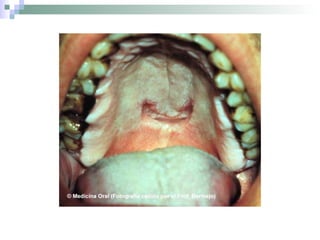

Fase 2: Sífilis primária Aparece um lesão rosada ou ulcerada, geralmente indolor que podendo passar despercebida (no pénis, vagina, boca ou ânus). Gânglios linfáticos inchados;

Fase 2: Sífilisprimária Aparece um lesão rosada ou ulcerada, geralmente indolor que podendo passar despercebida (no pénis, vagina, boca ou ânus). Gânglios linfáticos inchados;